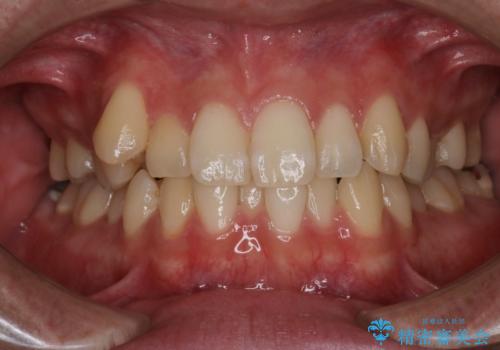

【審美装置】非抜歯矯正で八重歯改善!